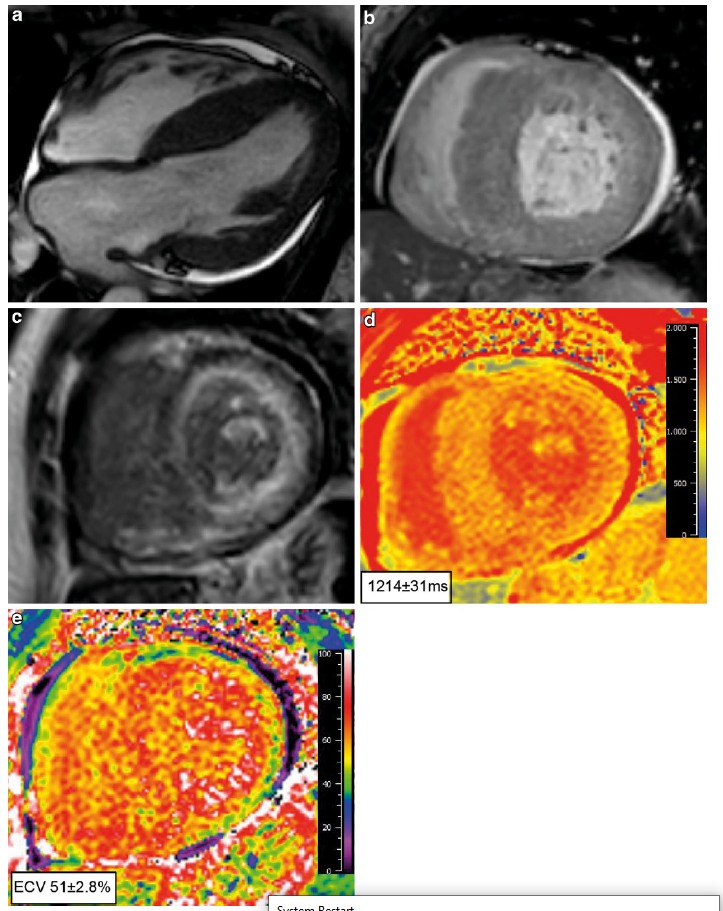

Beschrijving tonenOok een MRI kan u specifieke kenmerken voor cardiale amyloïdose tonen, bijvoorbeeld:

- transmurale of subendocardiale late gadolinium enhancement beeldvorming (LGE);

- diffuus atriaal LGE;

- rechterventrikel LGE;

- suboptimale nulstelling als gevolg van veranderde gadoliniumkinetiek;

- verhoogd extracellulair volume en verhoogde native T1-waardes.8

Een 4-kamer en korte as beeld met linkerventrikelhypertrofie, voornamelijk in de septale regio (a,b). Corresponderend korte as beeld dat subendocardiale LGE laat zien. Let op het verminderde signaal van de bloedpoel (donker bloed), specifiek voor cardiale amyloïdose (c). Native T1-analyse met verhoogde T1-waardes (d) en een verhoogd extracellulair volume (e). Overgenomen uit Neth Heart J 27, 525 -536 (2019)doi:10.1007/ s12471-019-1299-1 Oerlemans, M.I.F.J., Rutt en, K.H.G., Minnema, M.C. et al. Cardiac amyloidosis: the need for early diagnosis. Met toestemming van Bohn Stafl eu van Loghum. -